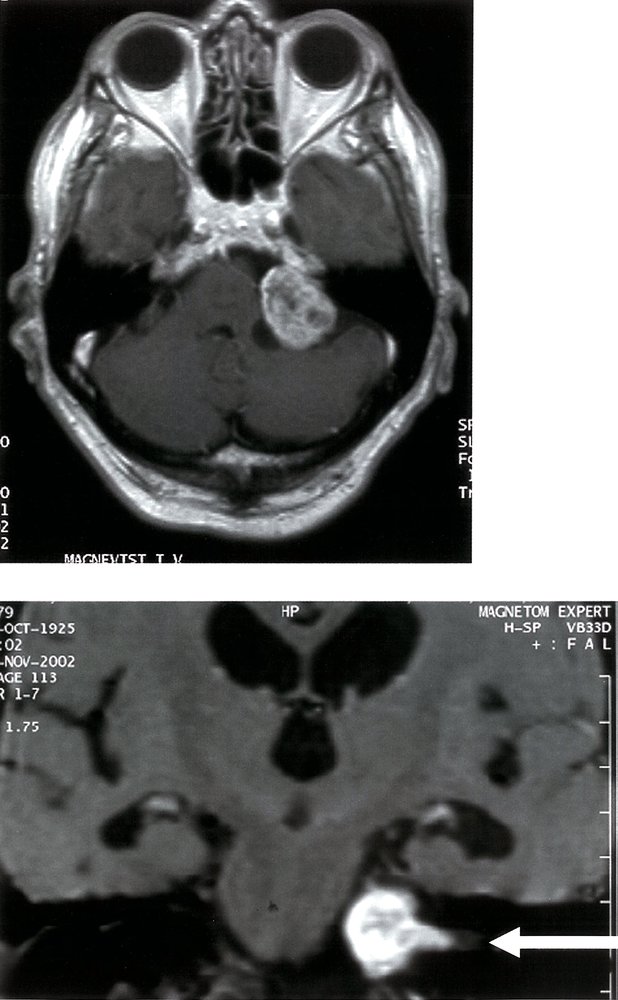

• Contrast MRI (imaging modality of choice)

• Recommended in patients with abnormal audiometric testing or high clinical suspicion of acoustic neuroma (cerebellopontine angle syndrome)

• CT with and without contrast is an alternative for those who cannot undergo MRI.

• Shows an enhancing lesion by the internal auditory canal, with possible extension into the cerebellopontine angle